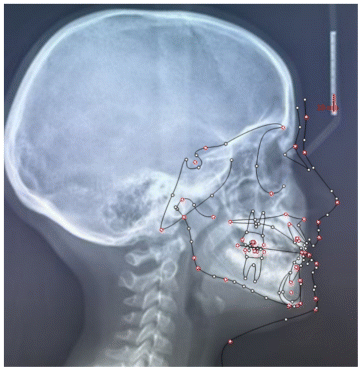

Case 2

The patient was a growing female child who presented during early mixed dentition with an anterior crossbite associated with a deep overbite and a marked sagittal discrepancy (Figures 12–19). The initial clinical examination revealed a negative overjet, complete anterior deep bite, and a functional Class III occlusal pattern. Extraoral assessment showed a flattened facial profile, while cephalometric analysis confirmed a skeletal imbalance characterized by increased SNA and SNB values, an ANB of 0°, negative Withs appraisal, and significant dentoalveolar compensations, including proclination of both upper and lower incisors (Table 3). The vertical pattern was predominantly hypodivergent, suggesting a high risk of unfavorable mandibular growth progression if left untreated. Given the patient’s young age and growth potential, an early interceptive treatment was planned to use the AMCOP® TC appliance, with the aim of correcting the anterior crossbite, improving neuromuscular balance, and guiding sagittal and vertical development during growth. The appliance was worn nightly and for additional daytime hours, according to patient compliance.

After 18 months of treatment, a clear clinical improvement was observed. Intraoral examination demonstrated complete correction of the anterior crossbite, with establishment of a positive overjet and normalization of the anterior occlusal relationship. The deep bite was reduced, allowing more functional anterior guidance. Occlusal relationships improved toward a stable dental Class I, and the need for excessive dentoalveolar compensation was reduced. Cephalometric reassessment showed an overall improvement in sagittal relationships and incisor inclinations, with a trend toward normalization of the previously altered parameters. These findings indicate that early functional therapy with the AMCOP® TC appliance was effective in intercepting the developing Class III malocclusion, improving occlusal function, and potentially reducing the severity of future skeletal discrepancies (Table 4).